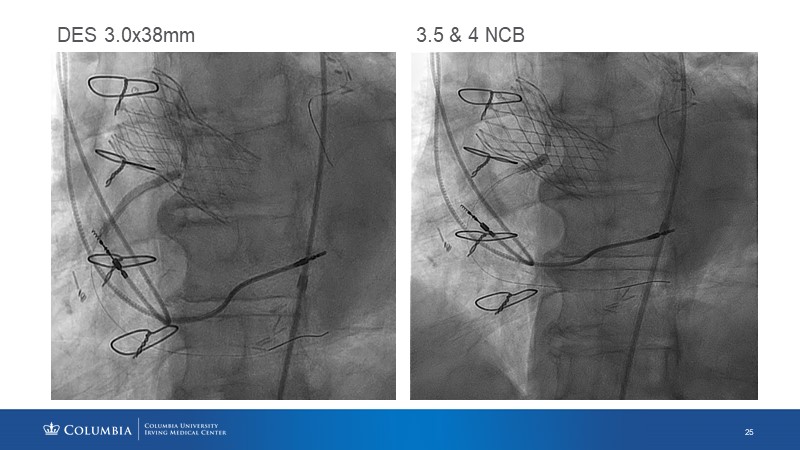

Through the presentation of real-life clinical cases, this session will allow you to discover the use of ALLEGRA for valve-in-valve TAVI, understand the management of coronary artery disease in TAVI patients, better detect when and how to protect coronary arteries during TAVI, or even learn how to perform commissural alignment with ALLEGRA.

- To understand the management of coronary artery disease in patients undergoing TAVI

- To better detect when and how to protect the coronary arteries during TAVI